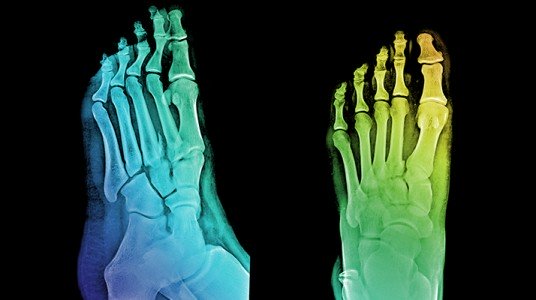

تشوهات أصابع القدم

يجب إجراء صورة شعاعية قبل الجراحة لدراسة وضع ونمط التشوه .